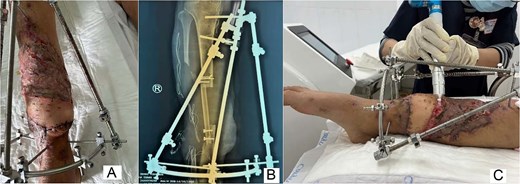

The wound was optimized using repeated debridement and circumferential negative-pressure wound therapy that enclosed the limb and external fixation (Fig. 2C), promoting granulation tissue (Fig. 3A). Definitive reconstruction (6 February 2025) used a vascularized pedicled fibular graft from the injured leg, fashioned to bridge the tibial defect and secured with screws and wires, while the external fixator maintained alignment (Fig. 3B and C).

Wound-bed preparation and bony reconstruction imaging. (A) Granulation tissue formation after serial debridement and continuous negative-pressure wound therapy. (B) Postoperative radiograph showing the vascularized pedicled fibular graft bridging the tibial defect; the external fixator maintained limb stability during recovery. (C) Postoperative three-dimensional computed tomography reconstruction confirming graft position spanning the tibial defect with stabilization by external fixation.

Soft-tissue reconstruction was completed with a latissimus dorsi free flap with a skin paddle. The thoracodorsal artery was anastomosed end-to-side to the posterior tibial artery under 3D magnification (Fig. 4A and B). Split-thickness skin grafting was applied over the muscle flap (Fig. 4C). The frame was modified to a semicircular configuration to improve stability and facilitate postoperative flap care.

Latissimus dorsi free flap transfer. (A) Intraoperative photograph of end-to-side microvascular anastomosis between the thoracodorsal artery and the posterior tibial artery. (B) Harvest of the latissimus dorsi free flap with a skin paddle based on the thoracodorsal vessels. (C) Early postoperative view demonstrating successful coverage of the lower-leg soft-tissue defect with the latissimus dorsi free flap.